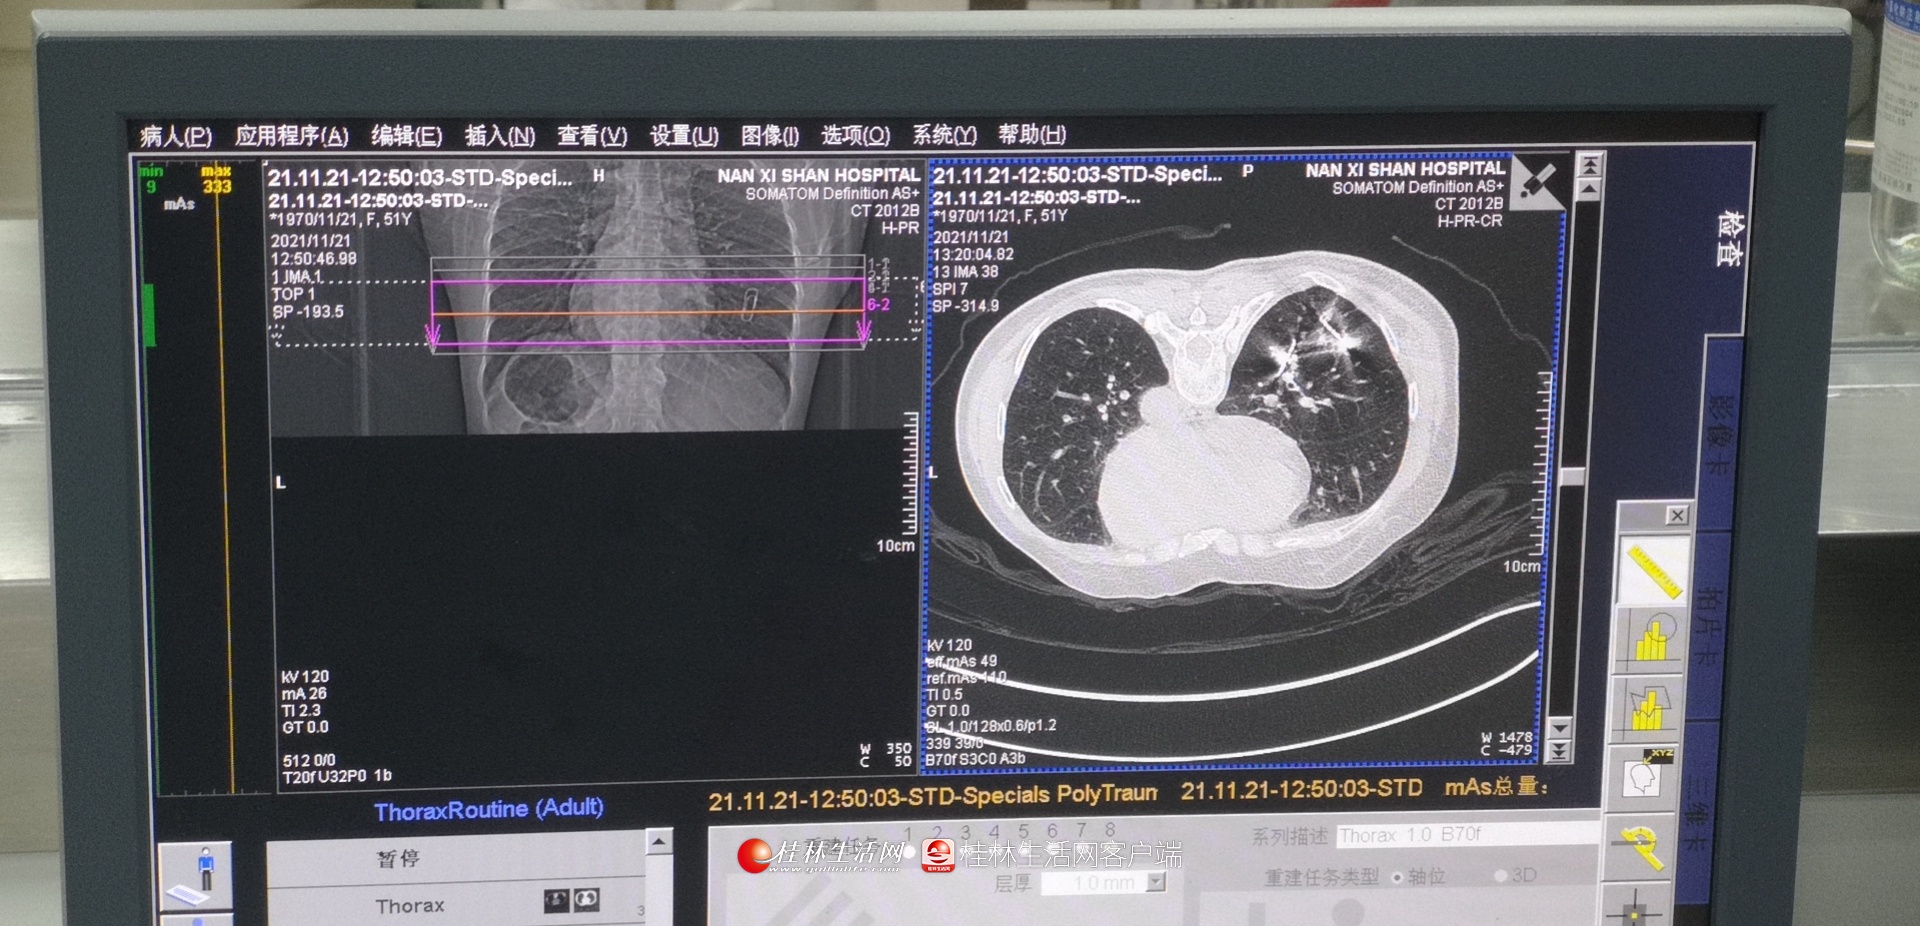

近日,广西壮族自治区南溪山医院呼吸与危重症医学科一区联合医学影像科顺利完成了两例在CT引导下进行的双肺结节微波消融术。

此次手术的两位患者莫女士和凌女士均为肺内两个IV类上肺结节病例。莫女士在1年前已经发现肺内结节,但未能进行积极治疗,内心十分忧虑;而凌女士2年前罹患左侧乳腺癌,此次复查发现左肺新发两个磨玻璃样结节,伴血管穿行,高度怀疑转移瘤。正在两人为自己的病情一筹莫展之时,得知南溪山医院能够开展CT引导下的肺结节微波消融术,不约而同到该院呼吸一病区就诊,经肺部CT检查发现两人均有双个肺结节病变,经呼吸一病区主任佘巍巍博士详细诊治,他认为肺内IV类磨玻璃结节恶性度高,若肺内出现两个IV类结节,则风险更高,考虑两位患者一般情况较差,且患者及家属担心外科手术风险及不能耐受手术,于是决定为她们采用CT引导下肺结节双针微波介入消融的手术方式,术后两位患者情况良好。消融后的实时影像结果显示病灶完全被覆盖,治疗效果立竿见影,莫女士和凌女士开心地向佘博士团队竖起了大拇指,感谢他们解决了自己的心头大患。